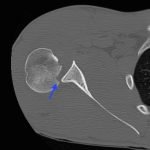

Radiographs demonstrated posterior displacement of the humeral head on the “Y” view (see white arrow) and widening of the glenohumeral joint space on anterior-posterior view (see red arrow). The findings were consistent with posterior dislocation and a Hill-Sachs type deformity. Sedation was performed and reduction was attempted using external rotation, traction counter-traction. An immediate “pop” was felt during the procedure. Post-procedure radiographs revealed a persistent posterior subluxation with interlocking at posterior glenoid. CT revealed posterior dislocation with acute depressed impaction deformity medial to the biceps groove with the humeral head perched on the posterior glenoid, interlocked at reverse Hill-Sachs deformity (see blue arrow).